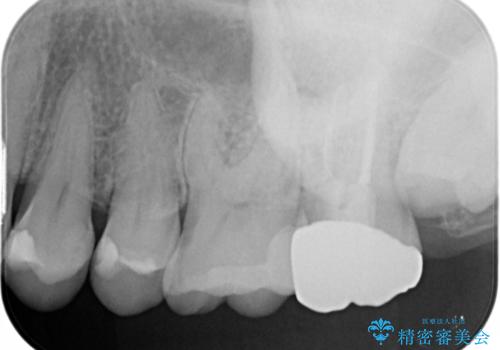

診断の結果、一番奥の歯は失活していたため精密根管治療から治療介入となりました。奥から2番目の歯にも大きな虫歯が認められたため、セラミックインレーによる補綴治療を行いました。 精密根管治療は患者様のご希望により、福本院長に行っていただきました。

根管治療をした歯は神経のある歯と比較して強度が下がり、長期的に破折のリスクが高まると言われています。破折のリスクを軽減させるため、根管治療を行った歯に対しては歯冠をすべて覆うクラウンという被せ物にて補綴処置を行います。

適合不良の補綴物は二次的な虫歯発生のリスクが高まります。

自費診療で用いられる材料は保険適応の材料に比べて、より精密で適合の良い被せ物作ることができるため、長期的な虫歯のリスクを大幅に減らすことが可能です。